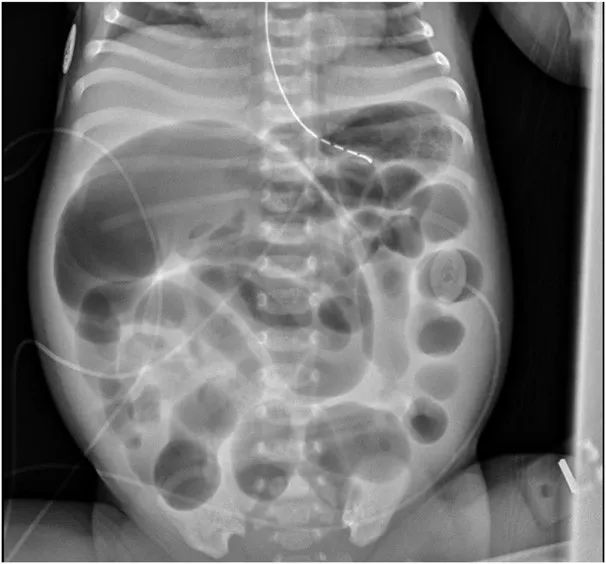

在产后第2天,患儿吃奶减少,腹部变得坚实和膨胀,呕吐,呕吐物为非血性和非胆汁性的。24小时内未排胎粪。腹部X光照片显示多个扩张的肠环,远端没有空气,符合远端肠梗阻的特征(图1)。